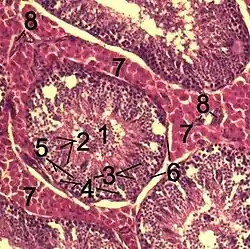

![]() Histological section through testicular parenchyma of a boar. 1 Lumen of convoluted part of the seminiferous tubules, 2 spermatids, 3 spermatocytes, 4 spermatogonia, 5 Sertoli cell, 6 myofibroblasts, 7 Leydig cells, 8 capillaries | |